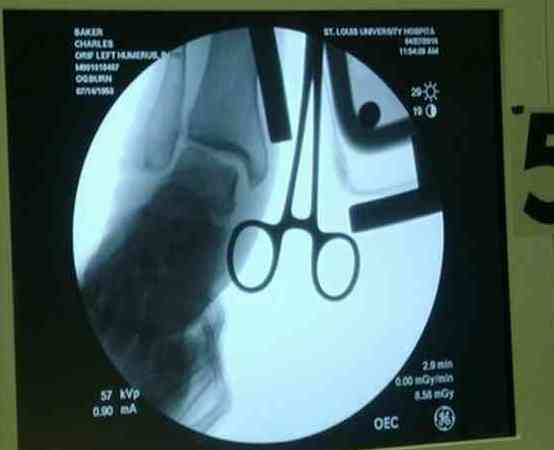

видели, все винты self tapping. Во втором случае у пациента с открытым многооскольчатым

переломом дистального плеча на 4 сутки выполнен остеосинтез. Обратите внимание =доступ без

резекции олекранона,медленная и ювелирная работа нетипичным для нас инструментом

закончена полным восстановлением анатомии локтевого сустава. В небольшой дефект залит

БМП\OP-1 Stryker ,продукт роста клеток человека в генной модификации\. Для профилактики

гетеротопической оссификации ряд врачей применяют облучение на 2-3 сутки.